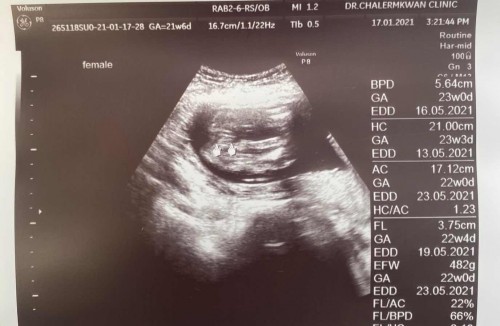

ตอนนี้ตั้งท้องได้ 23 วีค แม่ๆคนไหนเป็นตกขาว เป็นน้ำขุ่นๆไหลตอนตื่นนอนบ้างคะ ไม่คันนะคะ แต่จะเป็นเฉพาะตื่นนอนเช้าๆลุกจากที่นอน ส่วนระหว่างวันก็จะมีตกขาวเล็กน้อย เคยอ่านเจอว่ามีแม่ๆ เคยน้ำคร่ำรั่ว เลยอยากทราบว่า มันต่างกันยังไงคะแม่ ระหว่าง น้ำคร่ำ กับ ตกขาว##ขอบคุณล่วงหน้านะคะ #ขอคำแนะนำค่ะ #ขอคำแนะนำนค่ะ